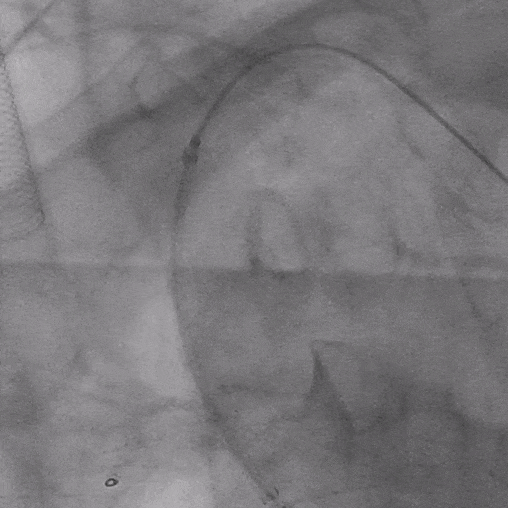

04. 沿左肱动脉引入5F Ver导管,头端垂直抵住主体支架覆膜,引入0.035″长泥鳅导丝配合导管顺利破膜,进入主动脉。

05. 0.035″长泥鳅导丝进一步超选进入降主动脉段,并沿右股动脉引入抓捕器抓取泥鳅导丝建立导丝路径,依次逐级使用4*40mm、6*40mm、8*40mm Amanda球囊扩张破膜处。期间可见明显受压切迹影。

06. 沿右股动脉引入8F长鞘,置入8*50mm Viabahn覆膜支架于开窗处,远端避开左椎动脉,近端超过覆膜支架1cm并完成释放。

07. 最后行全主动脉造影示LSA开窗支架重建良好,近端主体支架定位显影良好,腹主动脉右肾动脉、腹腔干动脉及肠系膜上动脉显影较支架植入前明显改善。